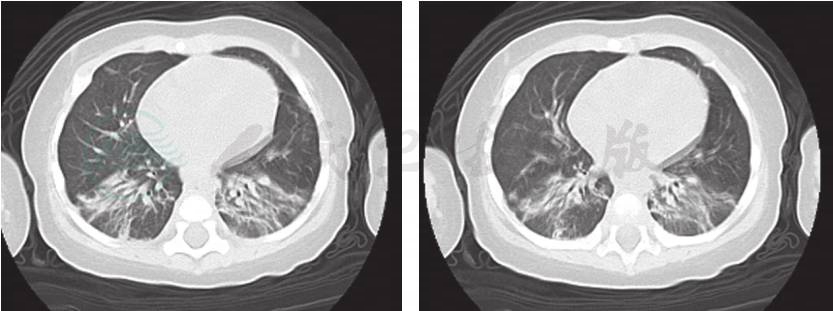

6.肺部CT(图1) 双肺段多发斑片影、结节影,以双肺下叶为著,未见胸腺影。

图1 入院后完善肺CT检查,提示:双肺段多发斑片影、结节影,以双肺下叶显著,未见胸腺影